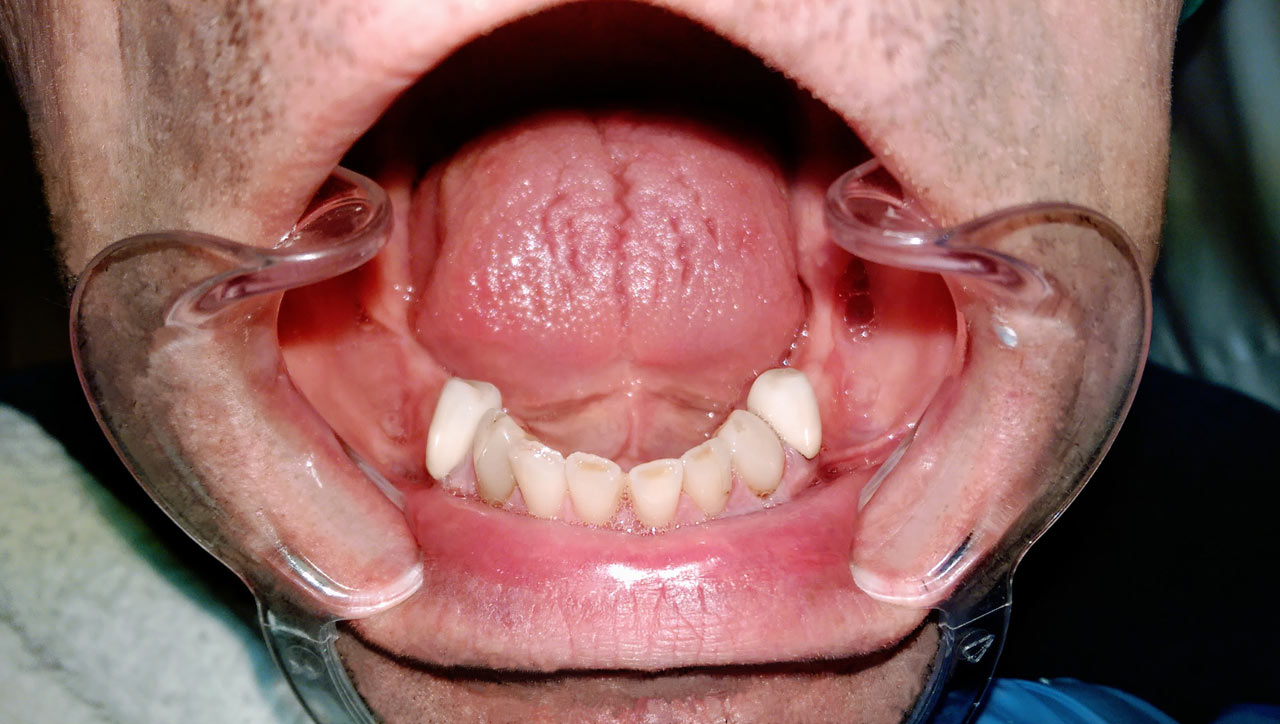

Alsó állcsont teljes rehabilitációja 72 óra alatt, azonnal terhelhető implantátumokkal súlyos paradontitisben szenvedő dohányzó páciens esetében. Az alsó állcsont fogai mind mozogtak az előrehaladott fogágypusztulás miatt.

A fogakat eltávolítottuk, a gyulladt, fertőzött csontot kitakarítottuk, kifertőtlenítettük, majd azonnal implantáltunk.

Svájci, IHDE márkájú, azonnal terhelhető implantátumokat helyzetünk be, és ezekre harmadnapra rögzített, hosszútávú, fémvázas, esztétikus műanyaggal leplezett hidat ragasztottunk be.

Ezt az ideiglenes hidat a sebek gyógyulása miatt használjuk, de tartóssága miatt véglegesként is használható.

A legtöbb esetben, ahogy itt is, 6 hónap múlva porcelán hídra cseréljük, a teljes gyógyulás után.